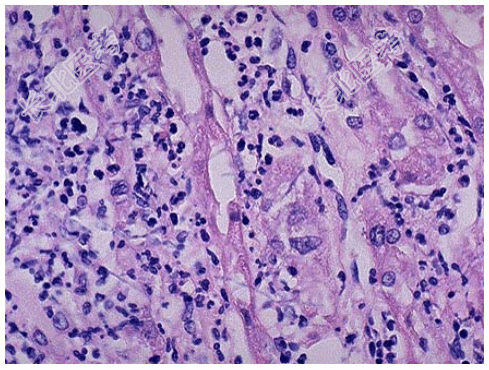

- [材料题] 死者,女性,28岁。因败血症死亡。发病初期曾有持续发热、腰痛、尿频、尿急、脓尿等症状。尸检见双肾肿大,包膜紧张,肾盂肾盏黏膜充血、水肿、表面有脓性分泌物,并可见小脓肿(如图),镜检如图所示。